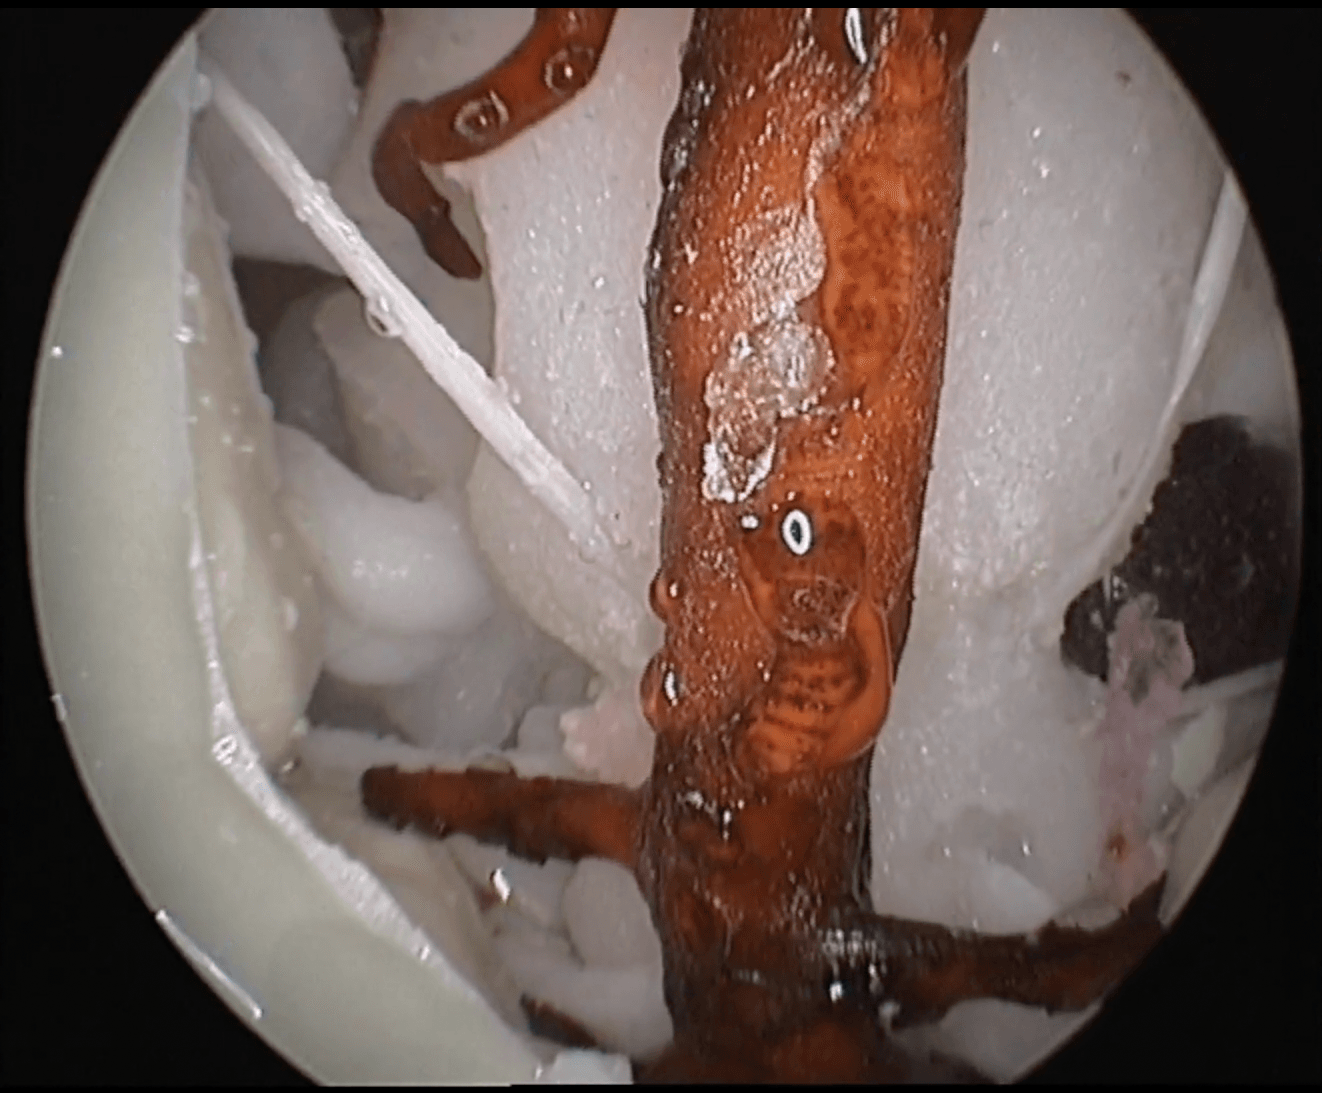

Human skull with all the craniometric points, fissures and canals. 1:1 scaled from a real human CT scan with similar drilling properties to the human bone. Includes skin, nasal mucosa, turbinates, septum, as well as a detailed intrasphenoidal anatomy.

The inner skull is covered with dura, and includes all cranial nerves, intracranial arteries as well as the brain, cerebellum and brainstem. Pathology included: pituitary adenoma and planum sphenoidale meningioma extracted from real cases and including the DICOM images for the preoperative planning.

Expand your endonasal surgery in the sagittal and coronal planes to gain space, and enjoy the anatomical journey!